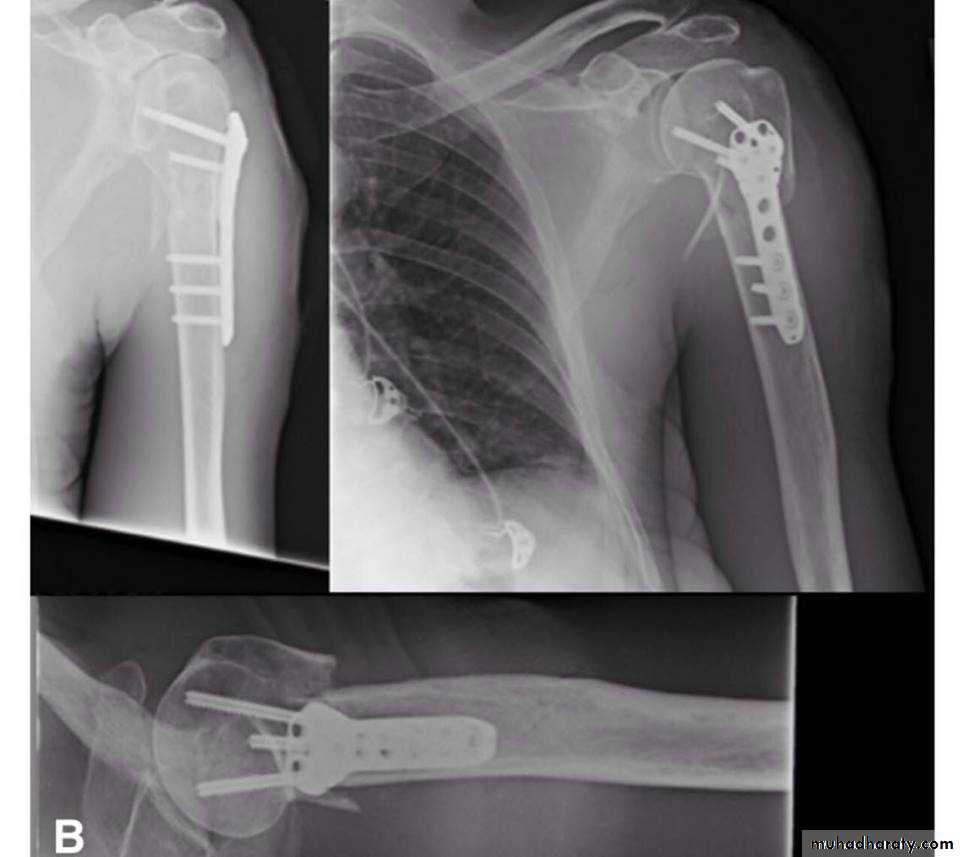

• Close reduction (MUA&sling ) 6weeks and active exercise later if failure

• Open reduction & internal fixation by percutaneous pinning plate and screws or intramedullary nailing21

TREATMENT

22

Plate and screws

23

24